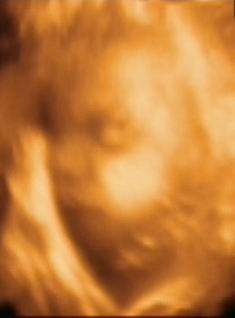

megvolt ma a 4D. Hát a mi kis madarunk elég kis szégyenlős fajta, ismét a lábaival takarta magát, nagyon nehezen tudtunk az arcocskájához férni, de azért sikerült egy-két képet csinálni. Holnap bescannelem, aztán felteszem. Olyan édes volt

Mikor keltegette a szonográfus, enyhe hasmozgatással, akkor a 3. noszogatásra megébredt, majd egy nagyot csapott a kezével, mint aki azt mondja, hagyjatok már békén

Mindenesetre így is látszott a lényeg, hogy fejjel lefelé van, de elég furcsa pozícióban.

A feje van jobbra lent, majdnem középen, aztán a köldökemnél van a háta-hasa-feneke, majd a lába visszafordul a teste elé, egészen le a fejecskéjéig. Szóval olyan kis kifli formában helyezkedik el. Elég érdekes, enyhén jóga-pozitúra